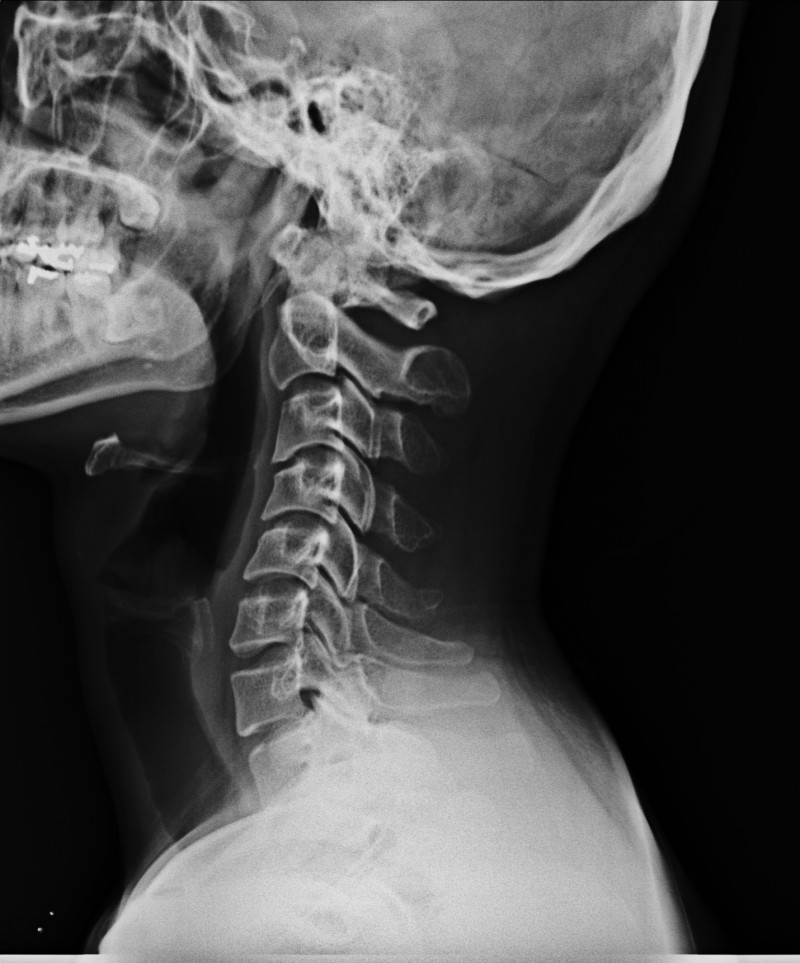

눈이 침침하고 뒤통수도 묵직하고 어깨도 결리고 여러가지로 답답함을 느낌니다.

저에 목엑스레이 사진입니다. 조언부탁드림니다. 감사합니다.